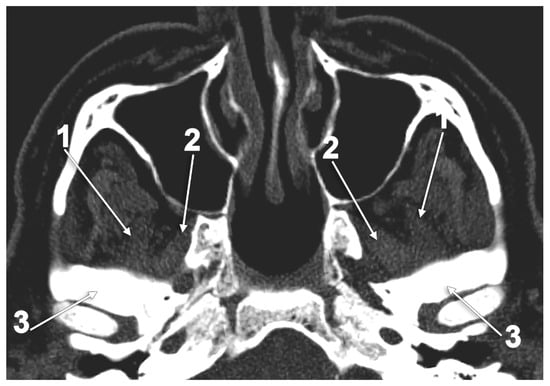

7. The Volume of the Lateral Pterygoid Muscle

The Atrophy and Hypertrophy of the Lateral Pterygoid Muscle